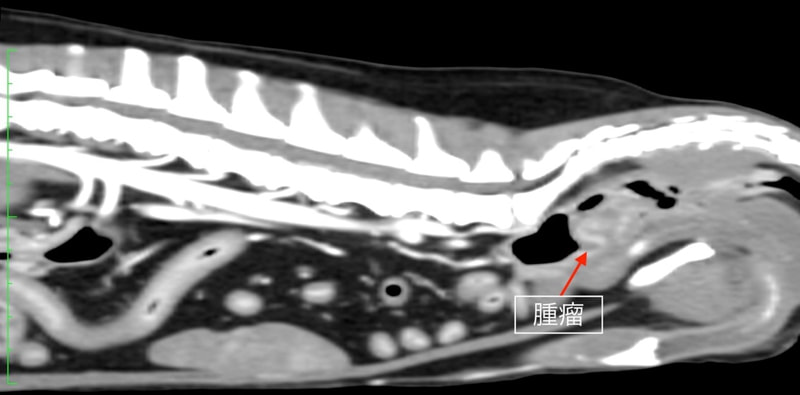

症例6:炎症性ポリープ

10歳 M・ダックスフント 去勢雄

主訴 血便

◎各種検査結果

・直腸検査 : 直腸内に腫瘤を確認

1ヶ月以上前から血便が認められるとのことで来院。最近は便の扁平化もみられるとのことでした。直腸検査にて肛門から約3cmの位置に直腸径を半分以上占めるφ1〜2cm大の腫瘤を確認しました。

腫瘤が比較的大きい為、早期の外科的切除を提案しました。術前のCT検査にて腫瘤が孤立性であり肺やリンパ節への明らかな転移像がみられないことを確認した後、直腸腫瘤の切除手術を行いました。

CT画像

◎追加検査

・病理検査結果 「炎症性ポリープ」

病理学的所見 : 多量の粘液を含む拡張した陰窩と肉芽組織の増生、リンパ球や好中球、マクロファージを主体とする炎症細胞の浸潤を認める。悪性所見を示す異型細胞浸潤や増殖は認められない。